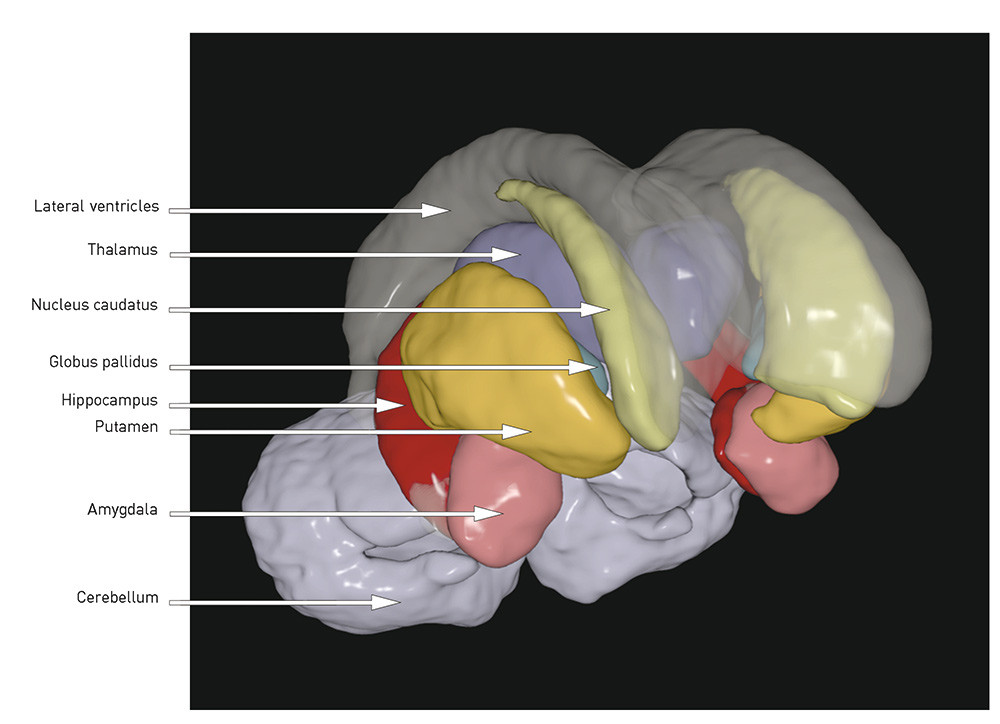

When the total volume is smaller and the ventricles enlarged, the question is whether there are certain regions or structures where the volume reduction is more pronounced. The following is a brief review of the best replicated findings (for illustration, see Figs. 1 and 2):

Fig. 1  Coronal section of T1-weighted MR image, automatic volume estimation using MRI post-processing tool FreeSurfer. R =…

Fig. 1 Coronal section of T1-weighted MR image, automatic volume estimation using MRI post-processing tool FreeSurfer. R = right, S = superior

The hippocampus is located medially in the temporal lobe of the brain and is important for verbal learning and memory. It is generally reported to be smaller in patients with schizophrenia than in healthy control subjects (4, 9), a finding we have also reported from two Scandinavian cohorts (7, 11, 12). In a recently published meta-analysis of 44 MRI studies, the effect size was found to be medium (d = – 0.48 and – 0.53 for the left and right hippocampus respectively) (13), and there was no difference between first-episode and chronic schizophrenia. That the changes were present at onset of the illness may indicate that the hippocampal volume reduction in schizophrenia is developmentally related. The hippocampal volume reduction may represent a loss of grey matter, which may be significant for cognitive functions like learning and memory, which have been shown to be impaired in schizophrenia (14).

A number of studies, including our own (7, 11, 15), as well as several meta-analyses (5, 16, 17), have demonstrated in cases of schizophrenia an enlarged volume of the basal ganglia, especially pronounced in the globus pallidus. The basal ganglia are rich in dopamine fibres, and changes may therefore be difficult to interpret since the structures are affected by antidopaminergic antipsychotics (18).

The thalamus, a mid-line structure that borders on the ventricles, has proved to be smaller in patients with schizophrenia (19). In one meta-analysis, an effect size has been found of d = – 0.32 (right) and d = – 0.33 (left) in chronic schizophrenia and d = – 0.45 (right) and d = – 0.48 (left) in first-episode schizophrenia (20). The thalamus functions as a key node in the brain’s cognitive processes, and one hypothesis is that the flow of information between different areas of the brain is disrupted in schizophrenia (21).

The cortex is a complex structure with sulci and gyri. The neurons in the cortex are among other things involved in volitionally controlled and complex cognitive processes. The first MRI studies found a smaller cortical volume, particularly in the frontal and temporal lobes (4). This volume loss has been replicated in a number of later studies and may reflect a reduction of neuropil (unmyelinated nerve cells, synapses and glial cells), as has been found in neuropathological post mortem studies of schizophrenia patients (22). A smaller volume may be caused by a reduction in thickness and/or area (volume = thickness x area). In our group’s study from Oslo, we found a thinner cortex and a smaller area and volume in schizophrenia, where the changes in volume were «driven» by the reduction in thickness (23). This finding is consistent with several other studies that show a thinner cortex, most pronounced in the frontal and temporal areas, in schizophrenia (24) – (26).